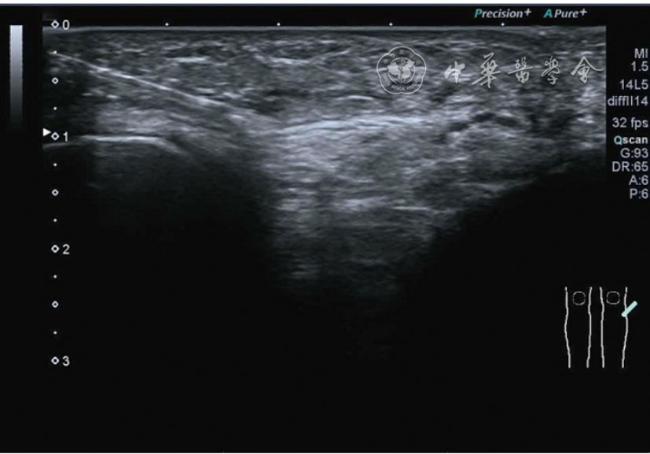

2.膝关节静态结构治疗。动力平衡失调后,继发静态结构变化,出现内外侧副韧带、交叉韧带、脂肪垫、半月板等结构变化。这里介绍半月板与交叉韧带的处理。(1)膝关节静态结构半月板治疗。在膝关节骨关节炎中主要是突出和损伤。突出主要发生于膝内翻引起的内侧半月板突出,引起内侧副韧带的张力增高。内侧半月板与内侧副韧带相连,是引起膝关节内侧疼痛的主要原因之一。治疗主要是针刀剥离松解,部分损伤可行PRP注射。①半月板突出针刀剥离松解治疗。针刀治疗主要是松解和减压,缓解疼痛,不能复位。以内侧半月板突出治疗为例。患者平卧位,髋轻度外展外旋,膝关节屈曲30°,膝下垫一软枕。选用10 MHz超声探头,穿刺区域常规消毒,探头涂抹耦合剂后套入无菌手套碘伏消毒或使用无菌耦合剂。将探头置于患者皮肤表面,内侧关节间隙长轴扫查,找到半月板突出最高点,用25G针头,抽吸1%利多卡因3 ml逐层麻醉直到半月板。选用直径1 mm的Ⅰ型2号针刀从头侧向足侧方向在内侧副韧带与半月板之间,以及半月板内部进行剥离松解3~5刀拔出针刀(图13),局部压迫5分钟,无菌敷料覆盖。②半月板损伤PRP注射治疗。半月板损伤主要表现为髌下痛,伸膝加重,查体在髌下髌韧带与侧副韧带之间,沿关节间隙有固定或局限性压痛,伸膝过程中尤为明显。MRI可示半月板断裂、损伤。如果出现绞索,严重影响功能需手术治疗。半月板损伤治疗,以注射PRP修复为主。以内侧半月板后角损伤为例。患者俯卧位,治疗前准备同半月板突出针刀剥离松解治疗。选用25G注射针头,抽取1%利多卡因2 ml局部麻醉后,制取1.5 ml PRP,穿刺到达半月板撕裂处注射,注射完毕后出针(图14),局部压迫2分钟,无菌敷料覆盖。(2)膝关节静态结构交叉韧带治疗。膝关节骨关节炎交叉韧带损伤多为部分损伤,治疗早期主要为药物或PRP注射,效果不佳时针刀做止点松解。①后交叉韧带损伤药物注射治疗。主要治疗韧带肿胀、无明显断裂患者。患者俯卧位,膝关节伸直位。一般选用10 MHz超声探头,治疗前准备同半月板突出针刀剥离松解治疗。将探头置于患者皮肤表面,后交叉韧带长轴扫查,找到胫骨止点,选用22G长针头,抽吸1%利多卡因3 ml+曲安奈德10 mg,从头侧向足侧方向穿刺到后交叉韧带胫骨止点部位的韧带表面进行注射,注射结束拔出针头(图15),局部压迫2分钟,无菌敷料覆盖。②前交叉韧带损伤PRP注射治疗。患者仰卧位,膝关节伸直。选用10 MHz超声探头,治疗前准备同半月板突出针刀剥离松解治疗。将探头置于患者皮肤表面,短轴扫查,找到前交叉韧带胫骨止点,选用25G针头,抽吸1%利多卡因3 ml逐层麻醉直到韧带止点部位,制备PRP 3 ml注射到前交叉韧带显露部位,注射结束拔出针头(图16),局部压迫2分钟,无菌敷料覆盖。③前交叉韧带损伤针刀剥离松解治疗。体位与治疗前准备同前交叉韧带损伤PRP注射治疗。短轴扫查找到前交叉韧带胫骨止点,选用25G针头,抽吸1%利多卡因3 ml逐层麻醉直到韧带止点部位,选用直径0.6 mm的Ⅰ型2号针刀从外侧向内侧于前交叉韧带胫骨止点部位剥离松解3~5刀拔出针刀(图17),局部压迫5分钟,无菌敷料覆盖。

图17 超声引导下前交叉韧带损伤针刀剥离松解治疗